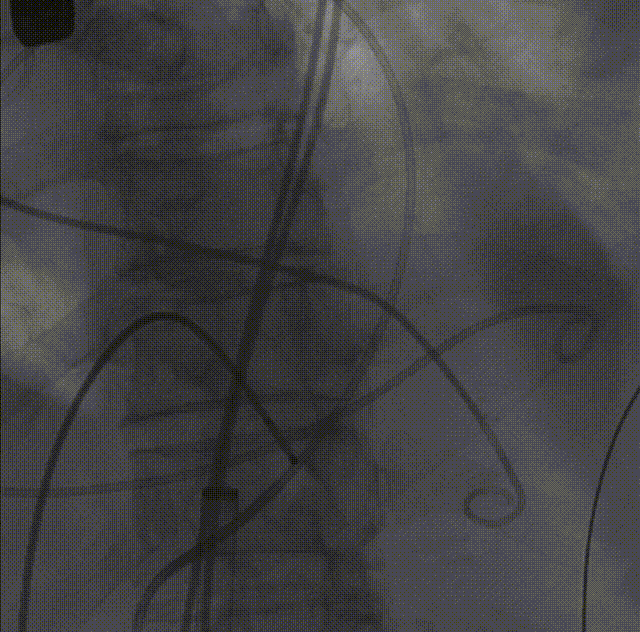

瓣膜内22mm球囊后扩张,左冠无显影

LM烟囱支架植入4.0*30mm